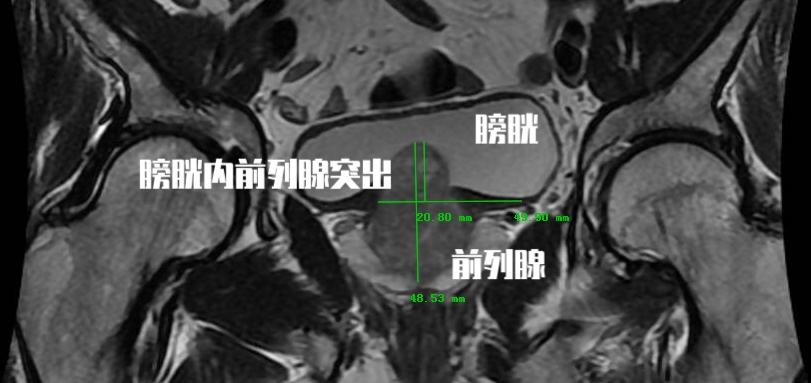

前列腺增生临床进展危险因素四:前列腺膀胱内突出度

这是一个彩超检查经常会报的指标,但是往往会被患者和医生所忽视。 前列腺膀胱内突出度是超声测得的前列腺矢状面下突入膀胱内的前列腺尖端至膀胱与前列腺交界平面的距离。 这是用于预测膀胱出口梗阻的重要指标。 这个突出程度越重,患者往往临床症状越重,同时需要手术治疗的可能性也越高!